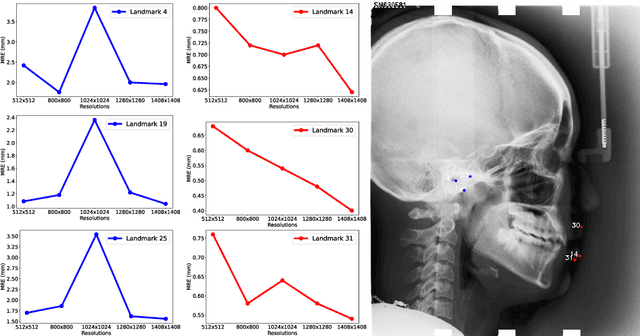

Cephalometric landmark detection on lateral skull X-ray images plays a crucial role in the diagnosis of certain dental diseases. Accurate and effective identification of these landmarks presents a significant challenge. Based on extensive data observations and quantitative analyses, we discovered that visual features from different receptive fields affect the detection accuracy of various landmarks differently. As a result, we employed an image pyramid structure, integrating multiple resolutions as input to train a series of models with different receptive fields, aiming to achieve the optimal feature combination for each landmark. Moreover, we applied several data augmentation techniques during training to enhance the model's robustness across various devices and measurement alternatives. We implemented this method in the Cephalometric Landmark Detection in Lateral X-ray Images 2023 Challenge and achieved a Mean Radial Error (MRE) of 1.62 mm and a Success Detection Rate (SDR) 2.0mm of 74.18% in the final testing phase.